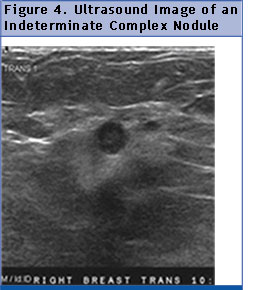

Benign Mimics of Malignancy on Breast Imaging MM Tyminski, DO; JE Watkins, MD, ET (images not shown). Ultrasound: 9 x 7 mm irregular hypoechoic mass with angular margins, no posterior features, and no Ultrasound: Complex cyst with solid components at the site of the palpable ... Document Retrieval